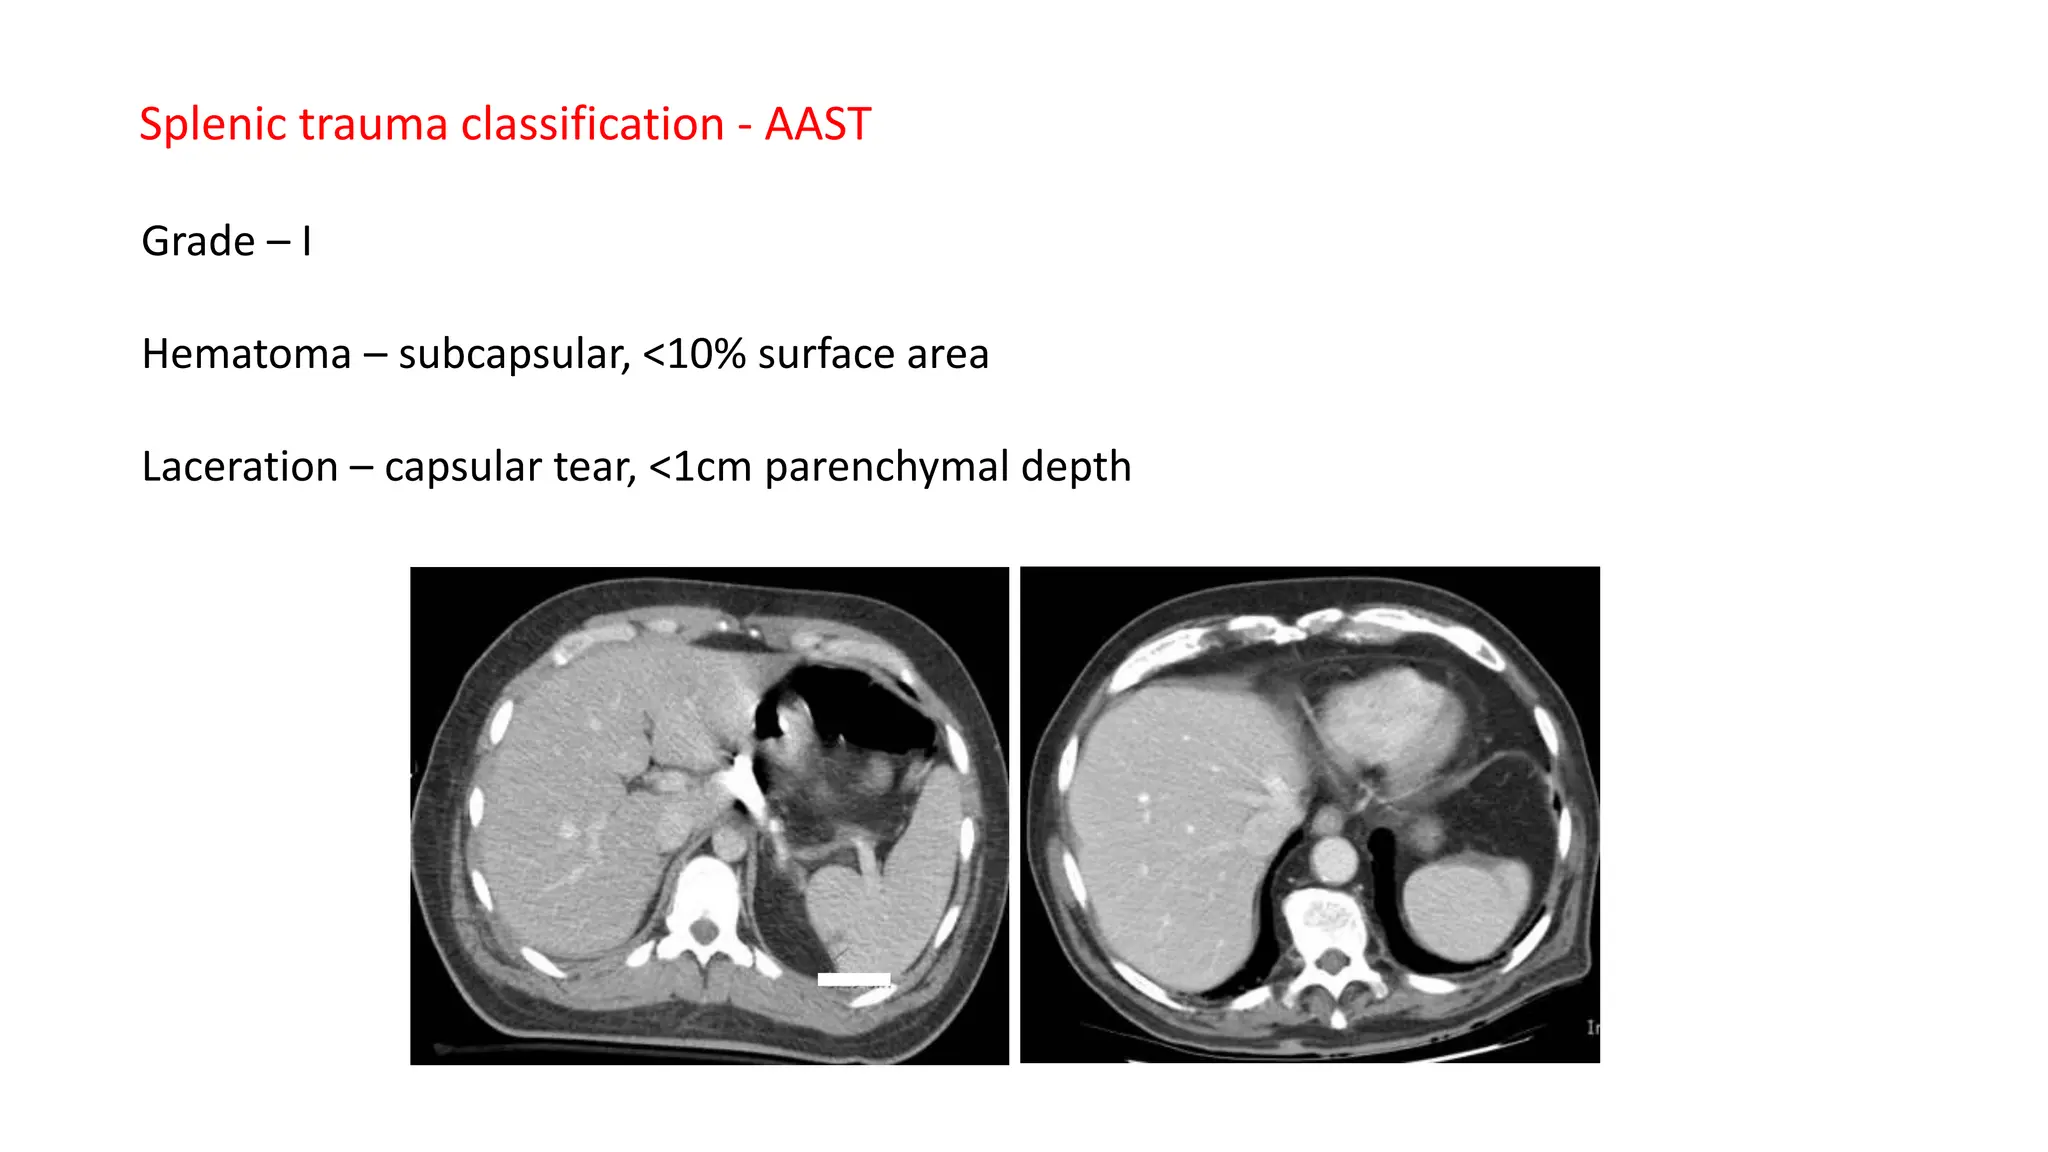

Grade I

Grade I injuries are the least severe and involve:

• Subcapsular hematoma less than 10% of the surface area.

• Capsular tear less than 1 cm in depth.